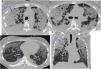

Más datosLa exposición al tabaco guarda una relación reconocida con el desarrollo de enfermedades de la vía aérea y el parénquima pulmonar. Aparte de la enfermedad pulmonar obstructiva crónica, en algunos individuos el humo del tabaco puede desencadenar mecanismos de daño intersticial que resultan en variadas alteraciones patológicas y fibrosis pulmonar. Se ha reconocido un grupo de entidades con una relación causal establecida con el tabaco, que incluye la bronquiolitis respiratoria con enfermedad pulmonar intersticial, la neumonía intersticial descamativa, la histiocitosis de células de Langerhans y la neumonía eosinófila aguda. Aunque el tabaco se considera factor de riesgo, aún es ambiguo su papel e impacto en el desarrollo de la fibrosis pulmonar idiopática, la entidad clínica diferenciada que se ha denominado combinación fibrosis pulmonar y enfisema, y la neumonía intersticial no específica. La definición de la fibrosis intersticial asociada al tabaco es relativamente reciente, con características histológicas diferenciadas. La interconexión probable entre los mecanismos que determinan la inflamación y la fibrosis pulmonar en todos estos procesos referidos se traduce con frecuencia en una superposición de rasgos histológicos, clínicos y radiológicos en el mismo paciente, que en algunos casos puede determinar patrones radiológicos de neumopatía intersticial no clasificables. Por ello es recomendable un abordaje combinado para el diagnóstico, que debe estar basado en la interpretación conjunta de las características histológicas y los hallazgos radiológicos, en el contexto clínico apropiado. Nuestro objetivo se centra en la descripción de los hallazgos radiológicos en la tomografía computarizada de alta resolución, en correlación con las manifestaciones clínicas y las alteraciones histológicas subyacentes al patrón radiológico.

Exposure to smoke is associated with the development of diseases of the airways and lung parenchyma. Apart from chronic obstructive pulmonary disease (COPD), in some individuals, tobacco smoke can also trigger mechanisms of interstitial damage that result in various pathological changes and pulmonary fibrosis. A causal relation has been established between tobacco smoke and a group of entities that includes respiratory bronchiolitis-associated interstitial lung disease (RB-ILD), desquamative interstitial pneumonia (DIP), Langerhans cell histiocytosis (LCH), and acute eosinophilic pneumonia (AEP). Smoking is considered a risk factor for idiopathic pulmonary fibrosis (IPF); however, the role and impact of smoking in the development of this differentiated clinical entity, which has also been called combined pulmonary fibrosis and emphysema (CPFE) as well as nonspecific interstitial pneumonia (NIP), remains to be determined. The definition of smoking-related interstitial fibrosis (SRIF) is relatively recent, with differentiated histological characteristics. The likely interconnection between the mechanisms involved in inflammation and pulmonary fibrosis in all these processes often results in an overlapping of clinical, radiological, and histological features in the same patient that can sometimes lead to radiological patterns of interstitial lung disease that are impossible to classify. For this reason, a combined approach to diagnosis is recommendable. This combined approach should be based on the joint interpretation of the histological and radiological findings while taking the clinical context into consideration. This paper aims to describe the high-resolution computed tomography (HRCT) findings in this group of disease entities in correlation with the clinical manifestations and histological changes underlying the radiological pattern.